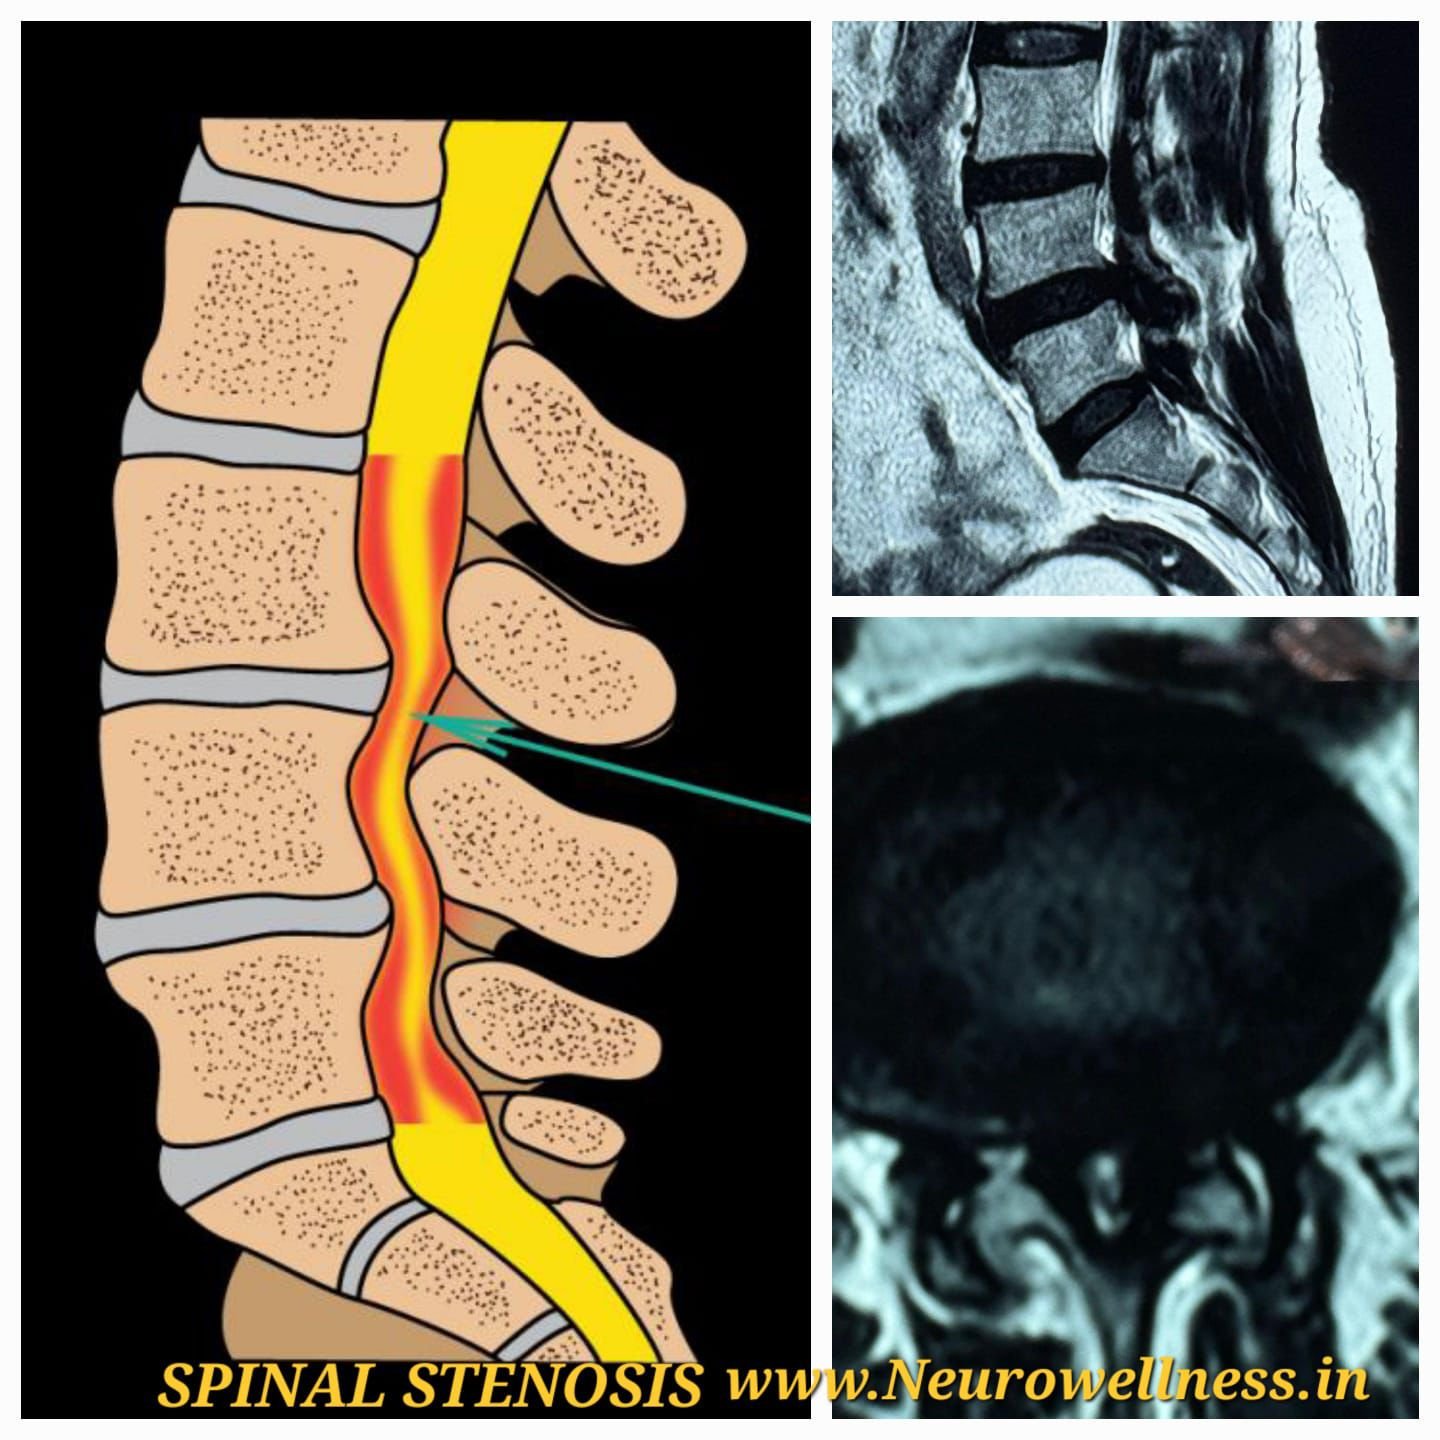

What Did the MRI Reveal?

MRI of the thoracic spine showed:

• Soft tissue mass at D8–D9 level

• Significant spinal cord compression

• Destruction of D8 and D9 vertebral bodies

• Structural instability

These findings were highly suggestive of spinal tuberculosis (Pott’s disease).

Additionally, imaging revealed severe lumbar canal stenosis at L4–L5, further increasing the risk of neurological compromise.